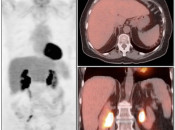

The normal liver demonstrates diffuse FDG uptake (typically greater than or equal to the spleen).

Many readers consider the uptake in the liver to represent the “background metabolic activity” for an exam.

For assessment of many lesions found in the body, the metabolic activity of the liver serves as the reference threshold by which to decide what is benign (uptake < liver) and what is malignant (uptake > liver).

Focal increased FDG uptake in the liver is always highly suspicious for malignancy. Very commonly, these malignant lesions may be poorly delineated on the co-registered CT images due to the lack of intravenous contrast administration.

Non-avid, low attenuation liver lesions are almost always benign (usually representing cysts, hemangiomas or fully treated malignant lesions), although some hepatocellular carcinomas can demonstrate only very mild metabolic activity.